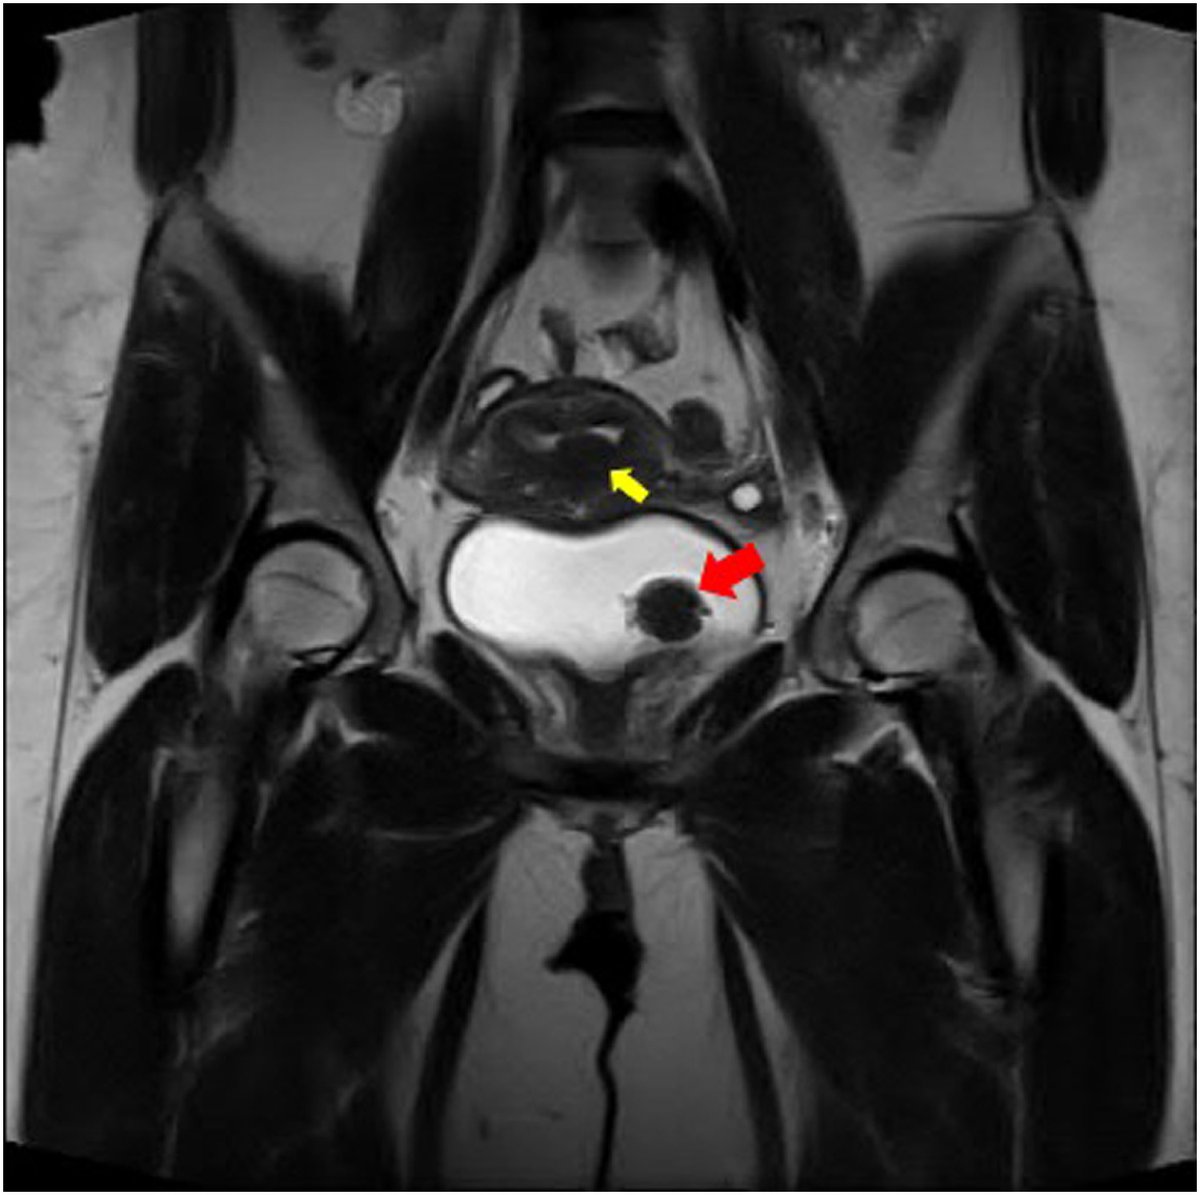

#Fibroids are not limited to the #uterus. In this case, one was found in the uterus --> heavy periods. A second was found within the bladder --> significant urinary symptoms. Check out publication for details! sciencedirect.com/science/articl… Ritchie Delara, MD, FACOG, FACS Mayo Clinic OB/GYN Mayo Clinic Urology